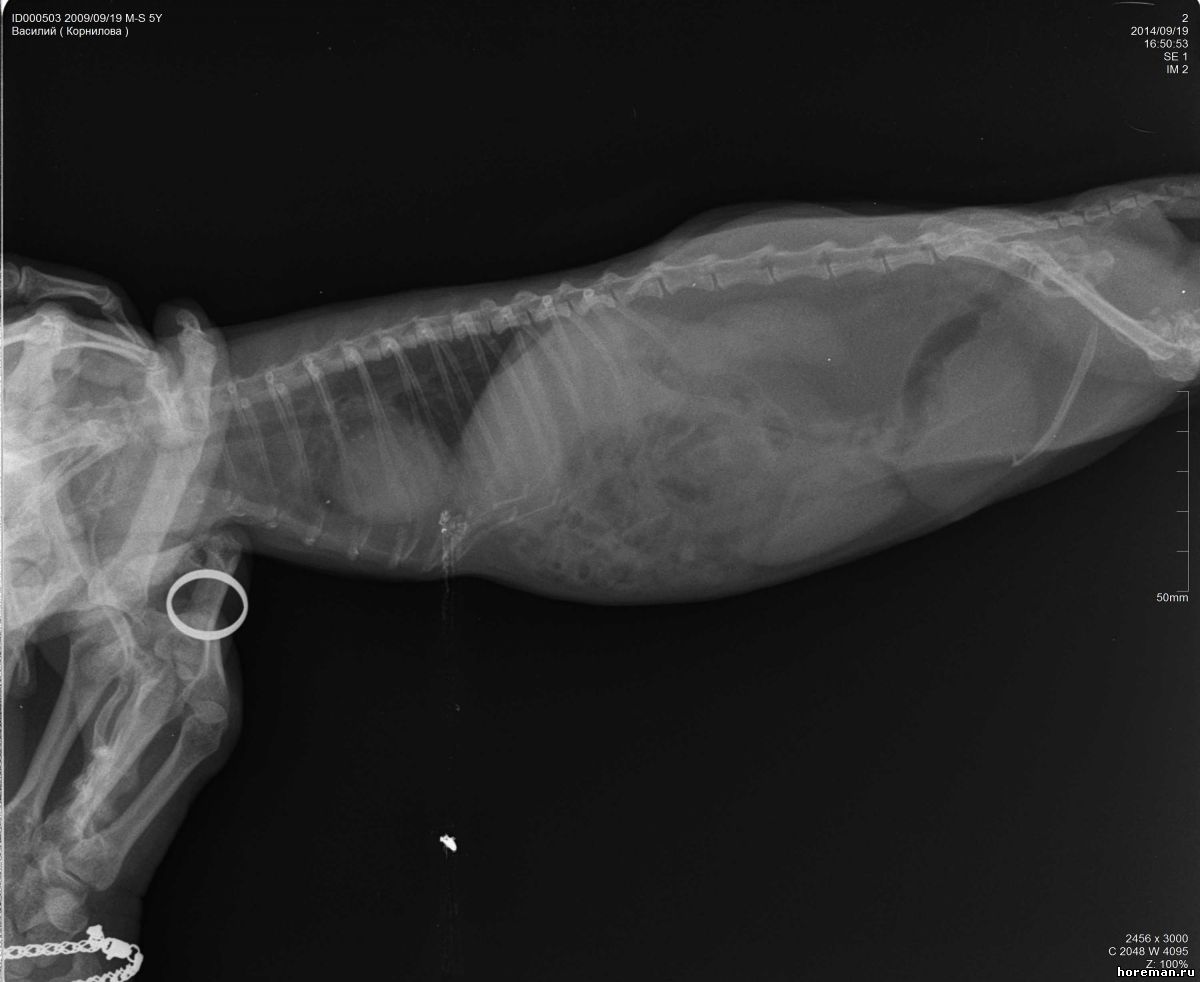

Добрый день! Нужно Ваше мнение по снимкам позвоночника моего хорька. 5 лет, кастрирован. Проблема с позвоночником, ползает на задних лапах, болевых ощущений нет, так же энергичен, игрив. Анализы все хорошие. Снимки не очень хорошего качества, завтра переделаем, но все же....

Подскажите.....Мнения нашего вета это защимление нервов в грудном отделе и что то там с позвонком выше поясницы, говорит нужна операция нейрохирургическая... :'(

Прикрепленный файл: 1991322.jpg (51.9 Kb) · 0357150.jpg (62.6 Kb) · 7876473.jpg (55.9 Kb)